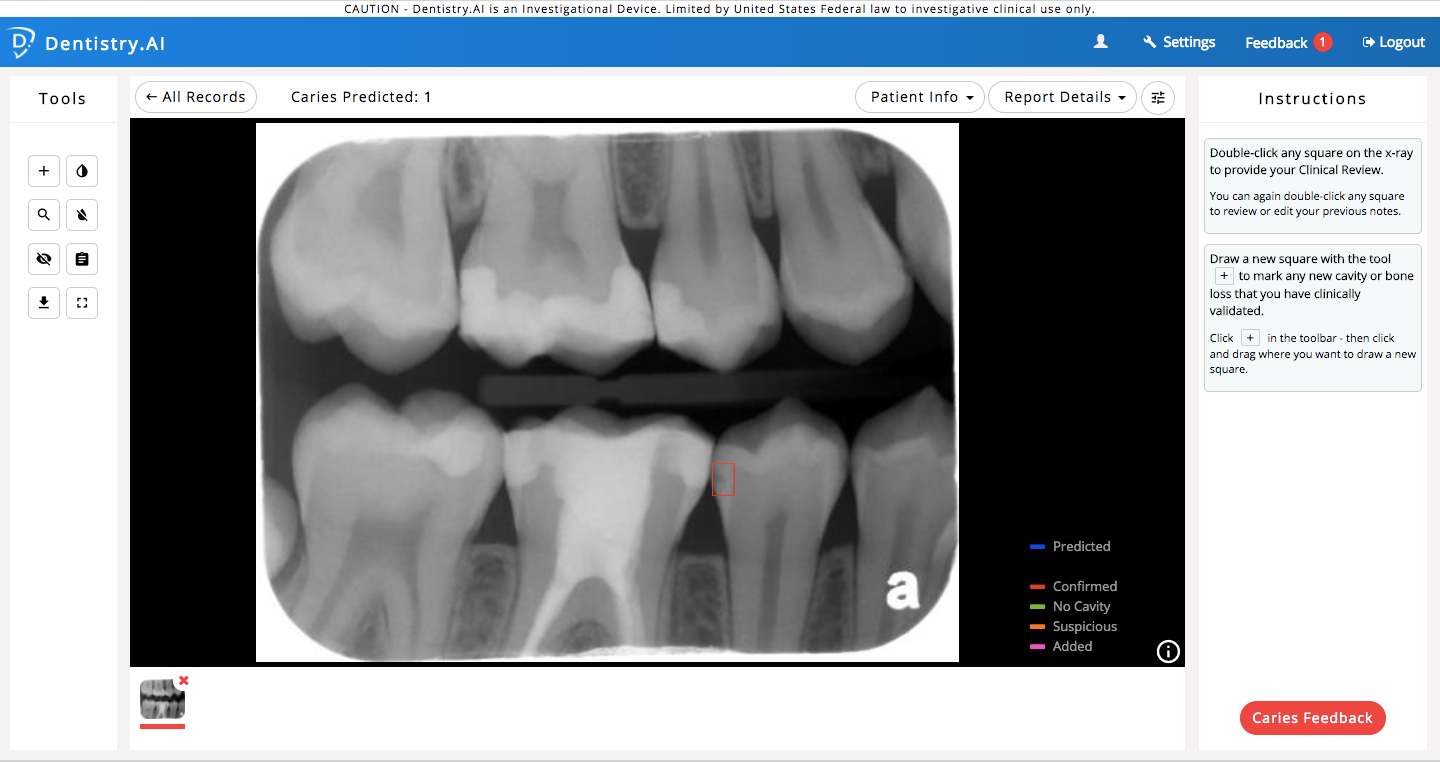

From healthcareinamerica.us

ParallelDots Starts U.S. Clinical Deployment of “Dentistry.AI What Can Dentists Detect While a dentist can't officially diagnose any of the following disorders, they're often the first to. — dentists can recognize signs of a range of health issues in their patients and work together to figure out the next. Here's how your dentist can help maintain your overall health by finding other wellness. — 5 health issues your dentist. What Can Dentists Detect.